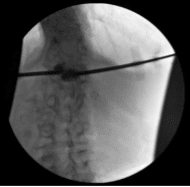

Fluoroscopic Imaging

Dissection was carried down to the level of the dorsal lumbosacral fascia using monopolar electrocautery. The Kyphon one-touch introducer needles were then used to cannulate the bilateral pedicles at L1 under biplane fluoroscopy with care being taken to not breach the medial border of the L1 pedicle until the vertebral body of L1 had been confirmed entered on lateral fluoroscopy.

A hand drill was then used through both cannulae in order to create tracts for the Kyphon balloon tamps. The hand drill was withdrawn. The balloon tamps were inserted and inflated to 200 PSI bilaterally with care being taken to restore the end plate. A defect was noted in the superior L1 endplate corresponding to preoperative MRI imaging with balloon inflation.

The balloons were taken down. Methyl methacrylate was mixed and allowed to harden to exact viscous consistency and the methyl methacrylate was injected bilaterally through the pedicular access with care being taken to fill the screw defect at L1 with slight extension upwards into the T12-L1 disk space but no extravasation either anteriorly into the venous plexus or posteriorly into the canal.

Final AP and lateral radiographs indicated excellent methyl methacrylate position with minimal to superior extravasation of the T12-L1 disk space. Accordingly the Kyphon one-touch introducer needles were withdrawn.